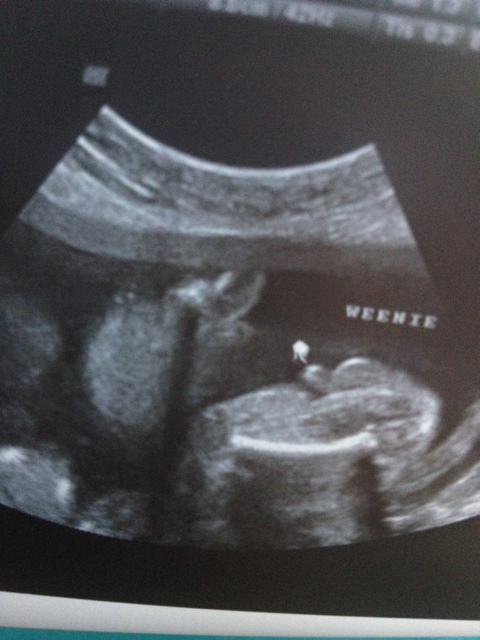

Attachment 12612Here is my 18 week scan. We still dont know what it is.. first u/s we were told 99% girl, second u/s we were told boy but not 100% sure. Can you tell me what you think based off of skull theory?

Sorry i cannot tell. Are you going to have a later scan? Didnt they do a potty shot? Cute baby though.

Looks like a boy for sure!

I am pretty sure both testicles and a penis are seen in that side shot you posted second, so I think it's a boy. That really doesn't look like a girl in the least. However, it's a side shot, instead of an under the bum shot, so I would want to confirm one more time. But I think I would function under the assumption that its a boy.

Baby boy. Do you have a pic of when you were told girl?

Looks like boy to me.

all boy!